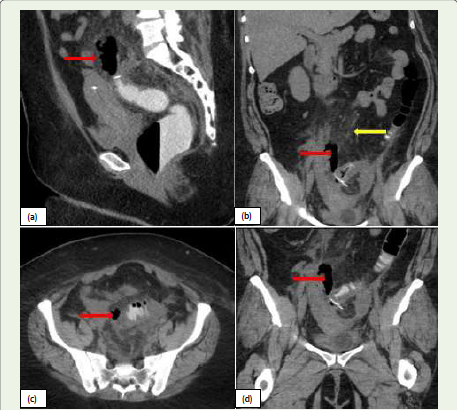

Figure 3: (a, b, c, d):Sagittal, Axial and coronal CT images of a 43-year-old

female, post laparoscopic sigmoid colectomy presents with abdominal pain

and signs of sepsis. CT abdomen and pelvis with rectal contrast demonstrate

extra luminal air loculi with mesenteric fat stranding (yellow arrow) adjacent

to the sigmoid anastomosis (red arrow), suggestive of anastomotic leak with

peritonitis in the lower pelvis. Additionally, reactive thickening of the sigmoid

colon is noted.